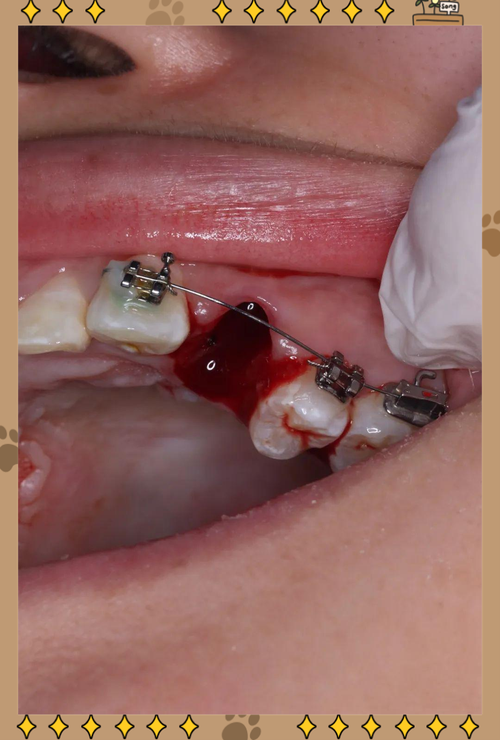

拔牙时机与间隙管理

正畸医生会在治疗初期(戴入固定矫治器1-3个月后)拔除下颌2号牙,拔牙后,并非立即关闭间隙,而是先通过“分差移动”或“整体移动”的方式调整牙齿位置: